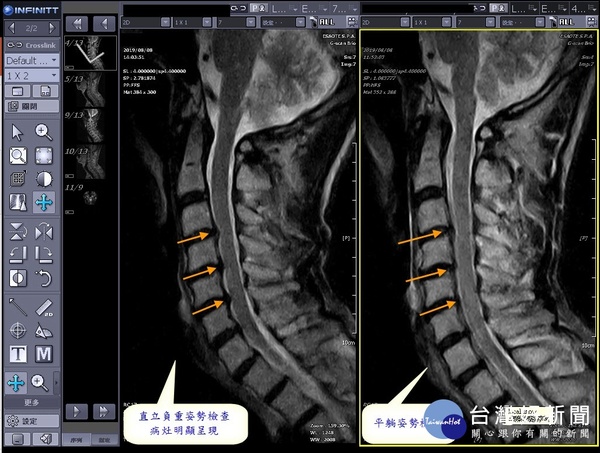

傳統平躺磁振造影(MRI)檢查,常有部份造影死角。彰化秀傳醫院引進最先進「動態負重磁振造影(MRI)」設備, 並於10日舉行揭牌啟用儀式,患者可直立、進行360度全身造影,照遍全身上下、 讓可疑病灶無所遁形,成為協助醫師對症治療新利器。

平躺核磁共振造影(MRI)檢查儀,在台灣各級醫院已相當普及, 所有傳統機型都是採取封閉式磁體與水平固定式檢查床, 當民眾平躺放鬆姿式下檢查, 與日常站立姿式解剖變化有相當大差異, 檢查結果因有部份造影死角,部份病灶常會被忽略,產生診斷盲點。

秀傳脊椎骨科胡名賢主任強調,引近「動態負重磁振造影(MRI)」之後,在多樣檢查參數配合下,可讓患者躺著、 站著或調整各關節角度來進行檢查, 可幫臨床醫師提供更多有價值診斷參考,為患者做出更佳、 更準確治療方針。